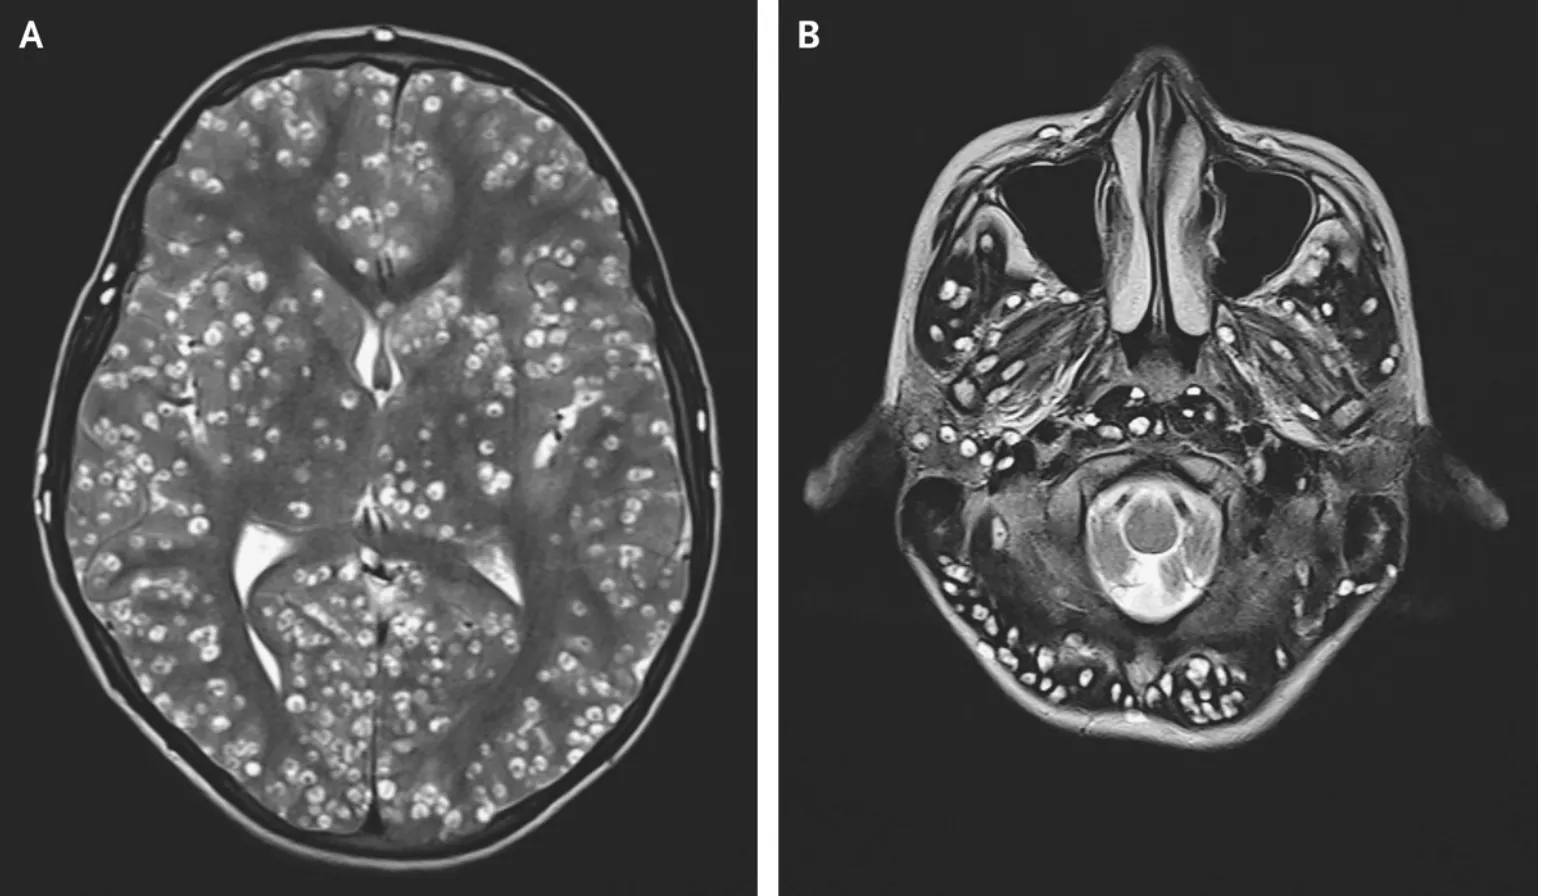

Ler mais Parasita

ParasitaToxoplasmose

Parasitose relacionada a alimentos contaminados, solo e contato com fezes de felinos.

Ler mais Parasita

ParasitaGiardíase

Infecção intestinal transmitida pela ingestão de água ou alimentos contaminados.

Ler mais Parasita

ParasitaAncilostomose

Helmintíase com transmissão pelo solo e possível penetração de larvas pela pele.

Ler mais Parasita

ParasitaCisticercose

Infecção tecidual causada pela forma larvária da Taenia solium.

Ler maisAprenda medicina de forma visual.